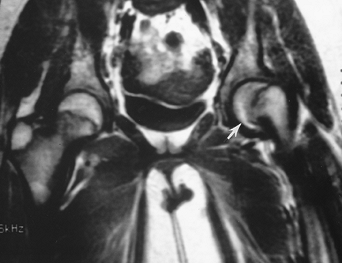

![]() |

FIGURE 4-51 AP (A) and oblique frog-leg views (B,C) of a slipped capital femoral epiphysis on the left. AP view (A) shows osteopenia and widening of the physis (arrows). Note the line along the lateral neck does not intersect the ossified epiphysis. The right hip (B) is normal. The displacement of the capital epiphysis on the metaphysis (lines) is obvious on the frog-leg oblique view (C).